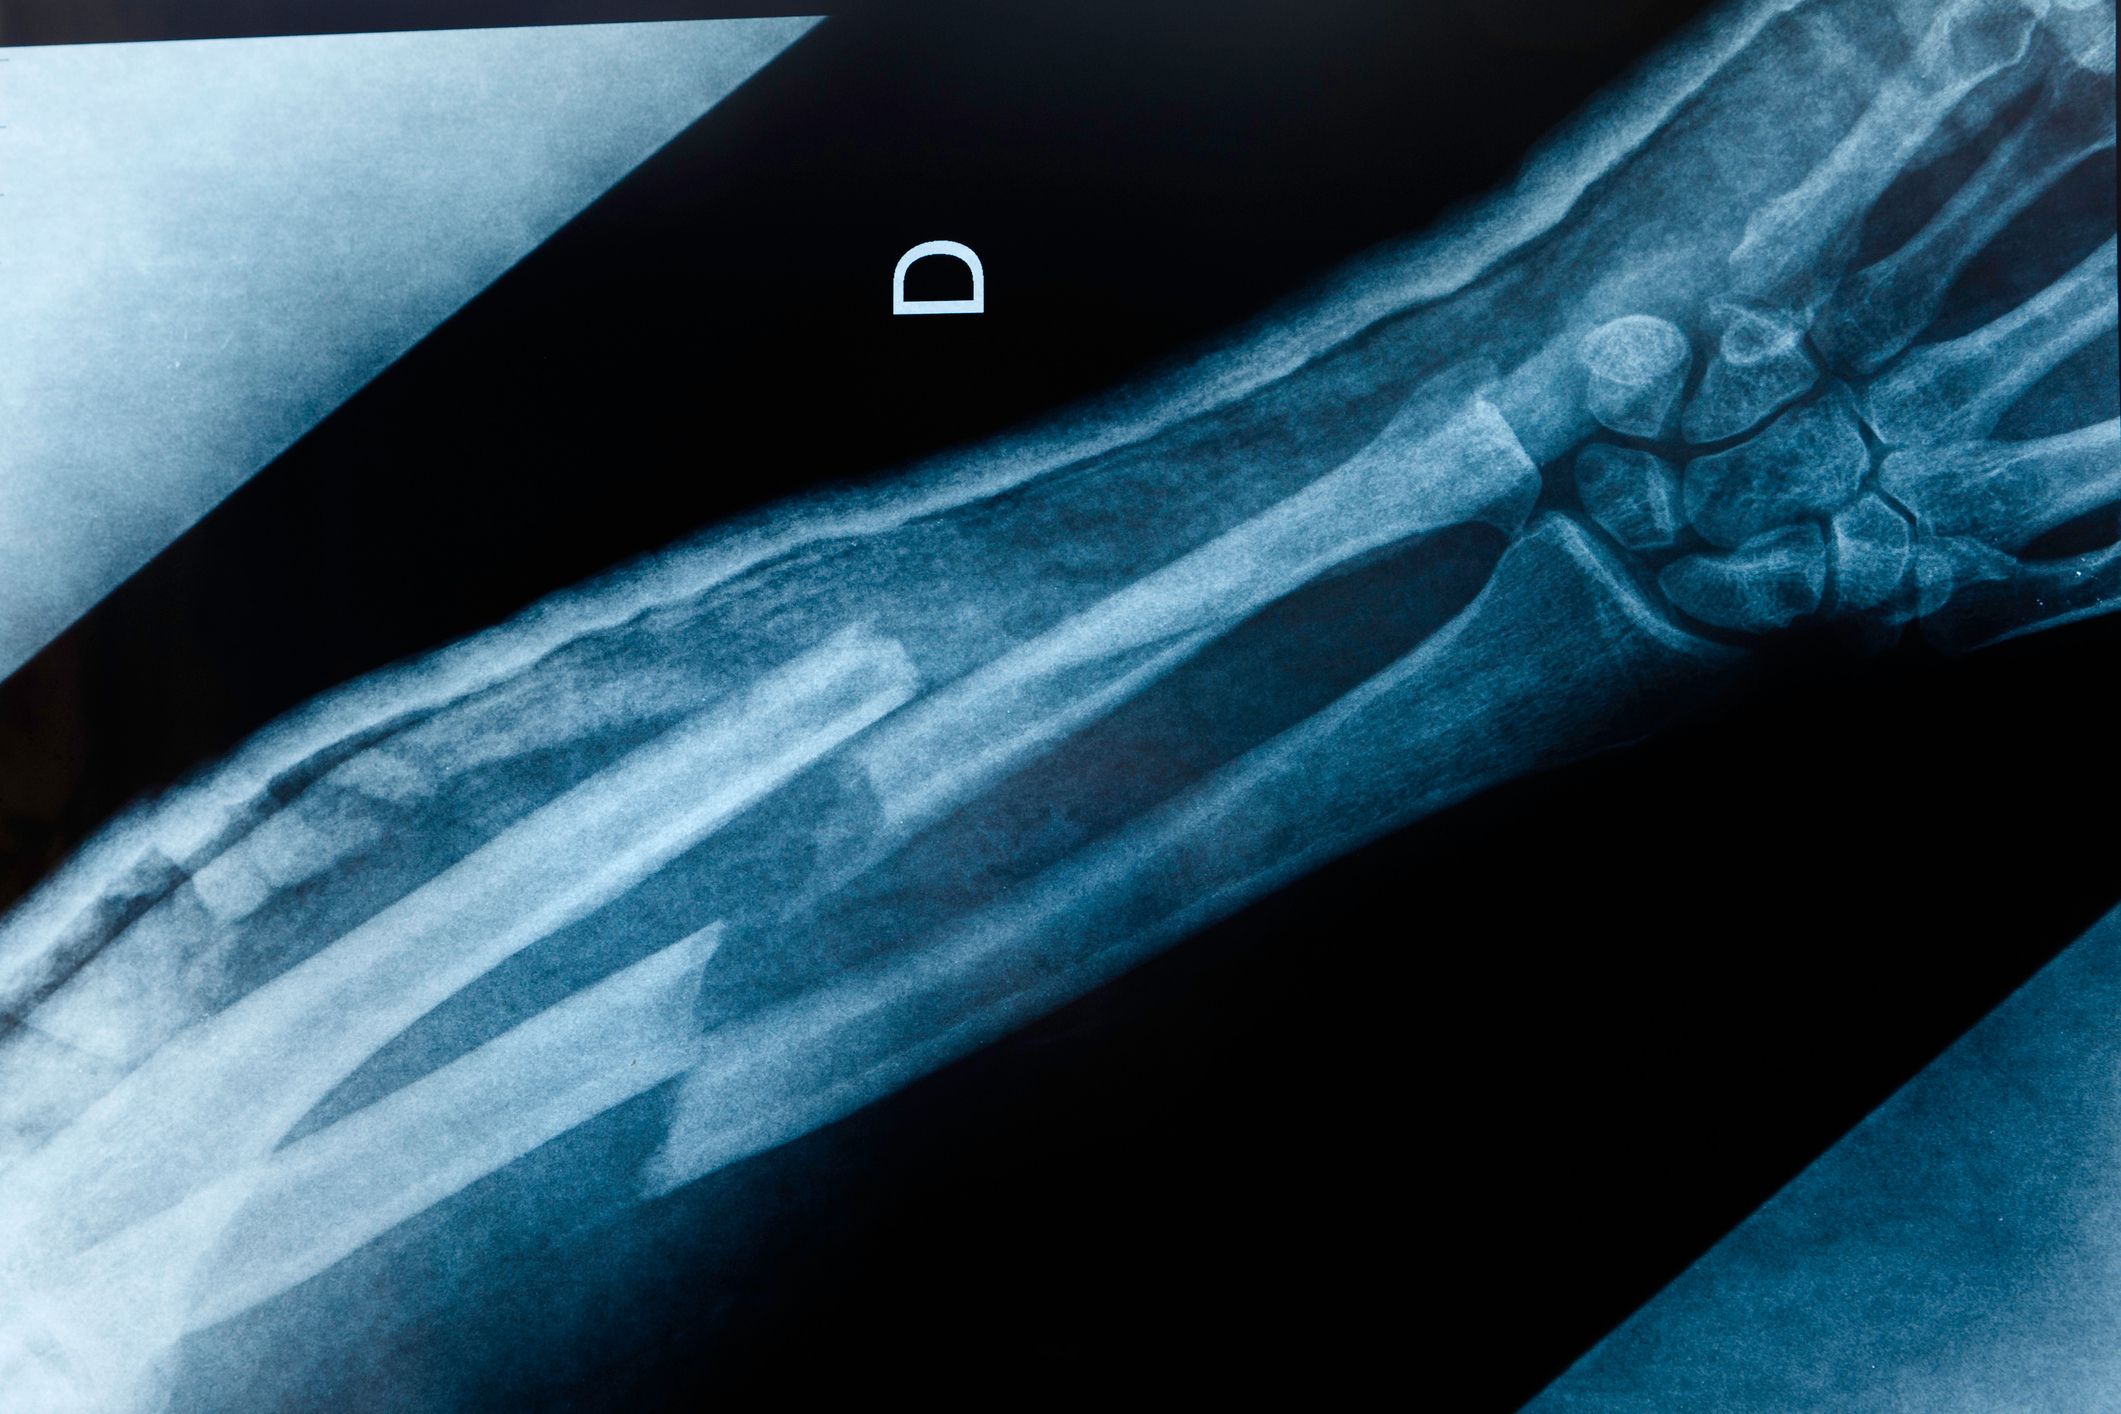

Osteoporosis affects about 3.8 million people in the UK. The disorder causes bones to become fragile due to low bone mass and deterioration in bone structure. This makes them more likely to break.

In one research study that tested the drug’s efficacy, abaloparatide reduced the risk of spine fractures by 88% compared to a placebo. The risk of other major fractures (such as hip, spine, wrist and upper arm) were reduced by 69%.